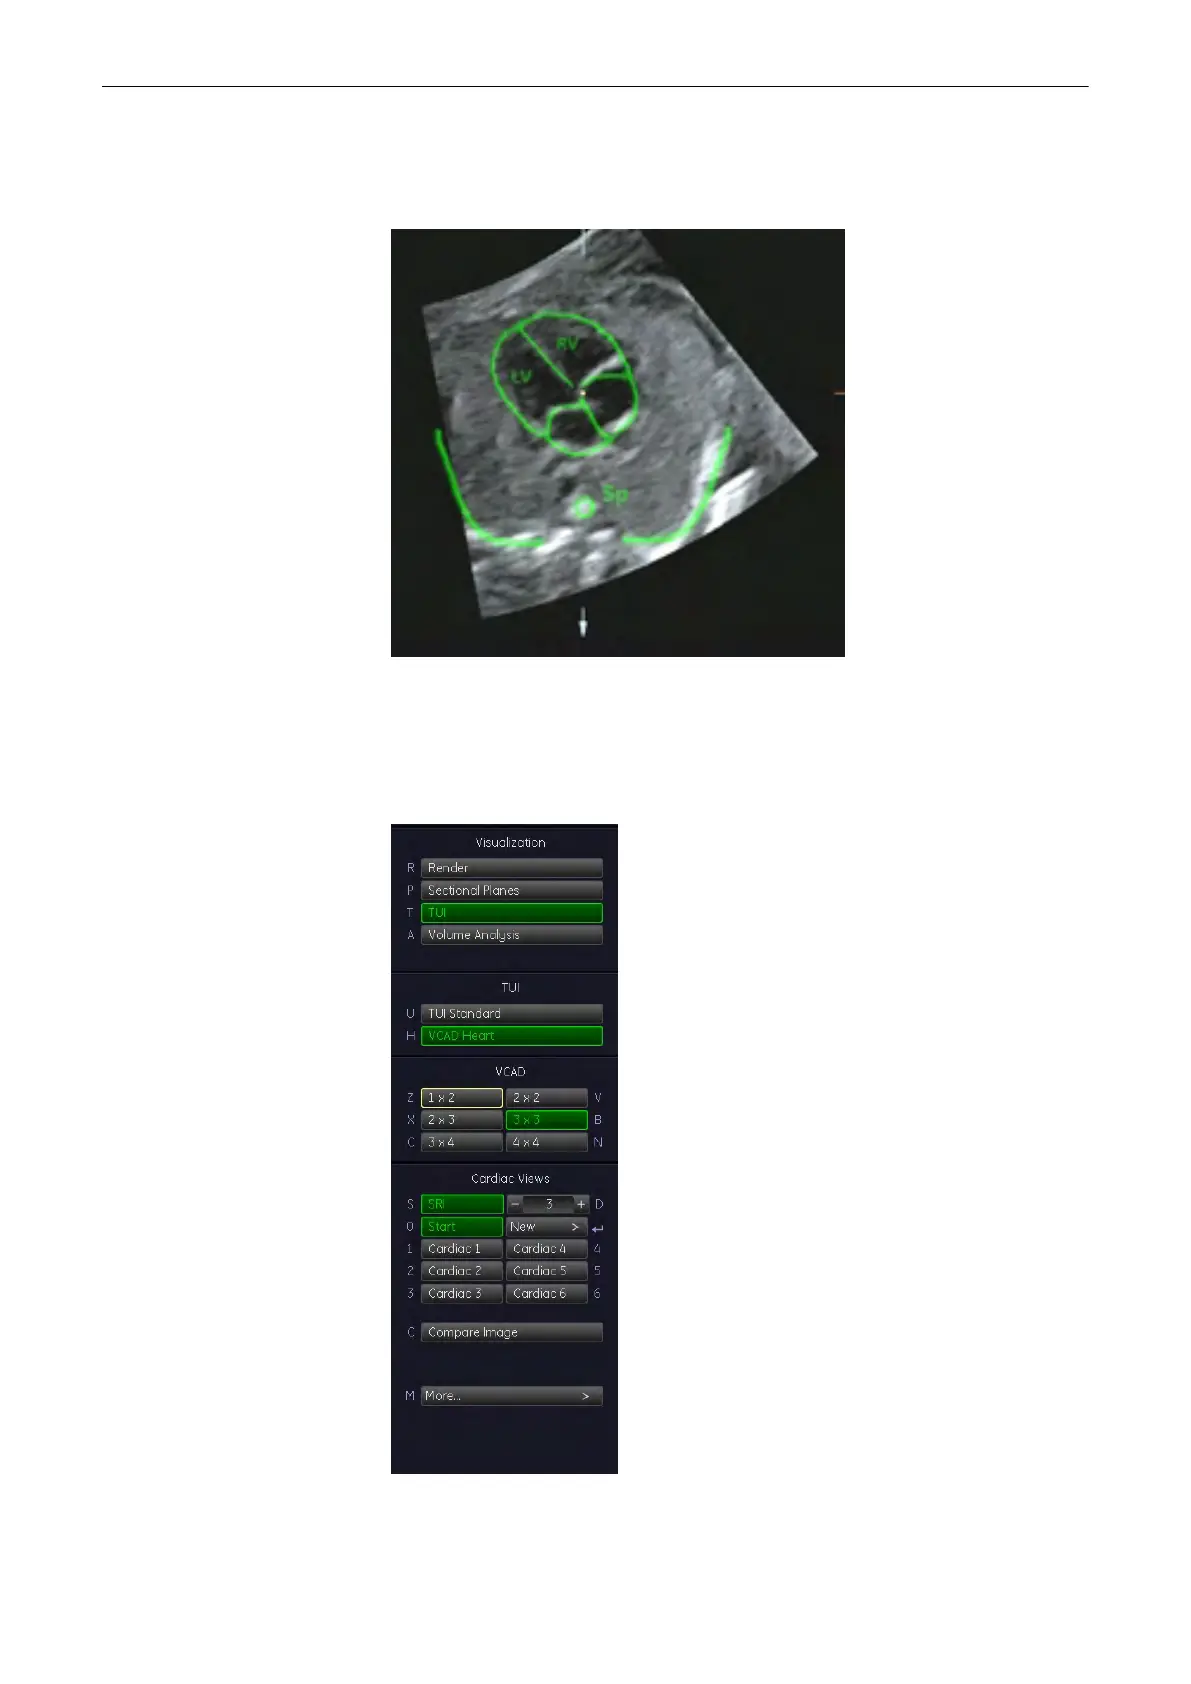

If you can already see the heart template on the monitor you can start adjusting. If you

cannot see the heart template on the monitor, press the [Plane Graphic] button. The

heart template appears.

3. Adjust the US image, using the X-, Y-, Z-rotary controls and the zoom button so that it

4. Press the [Set Starting Plane] button. If you have not been in TUI mode the monitor will

switch to TUI mode now. The following menu will appear on the menu area.

5. Now select the view you desire.